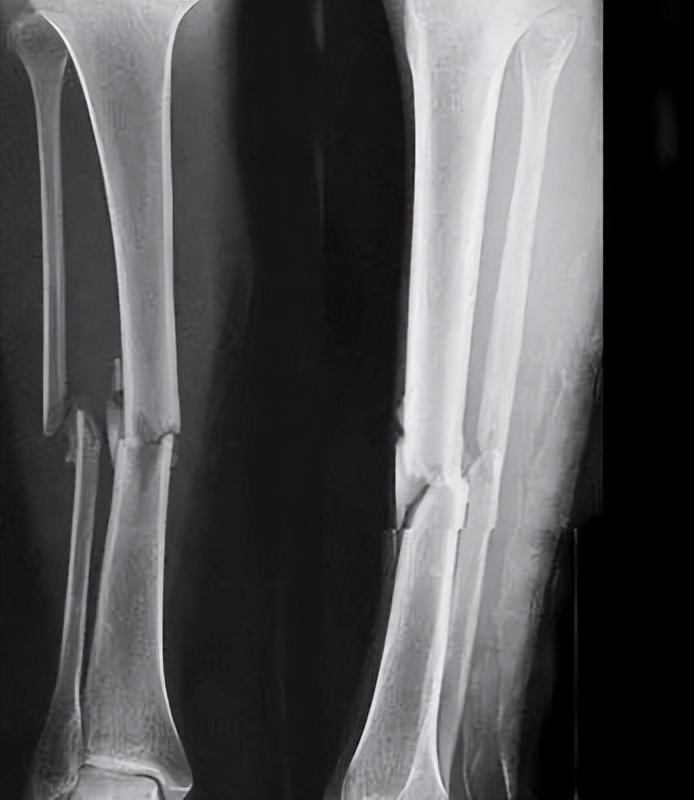

曾经骨折过能参军吗?

骨、关节、滑囊疾病或损伤及其后遗症,骨、关节畸形,胸廓畸形,习惯性脱臼,颈、胸、腰椎骨折史,腰椎间盘突出,强直性脊柱炎,影响肢体功能的腱鞘疾病,不合格。

以下情况合格:

1)可自行矫正的脊柱侧弯;

2)四肢单纯性骨折,治愈1年后,X线片显示骨折线消失,复位良好,无功能障碍及后遗症(条件兵除外);

3)关节弹响排除骨关节疾病或损伤,影响正常功能的;

4)大骨节病仅指、趾关节稍粗大,无自觉症状,无功能障碍(仅陆勤人员);

5)轻度胸廓畸形(条件兵除外)。